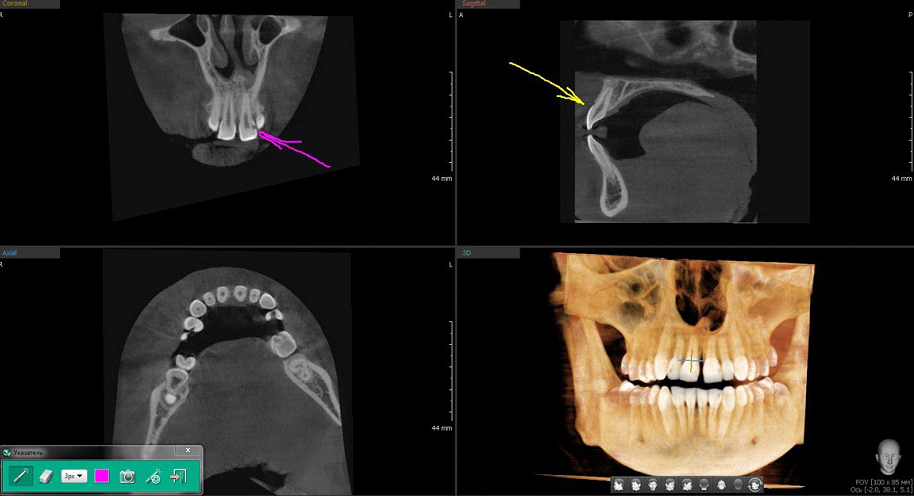

Здесь мы хорошо видим, что нужны разные проекции. Центральный резец верхней челюсти визуально в норме, один корень и колонковая часть в виде долотца. Розовая стрелка — он же, но в этой проекции отлично виден кариес.

Розовая стрелка — малый коренной зуб с кариесом (тёмное пятно по правому краю). Жёлтый маркер — большие коренные зубы, два-три корня, массивная коронка в виде кулачка. Зелёный — ретинированный «зуб мудрости», не прорежется никогда.